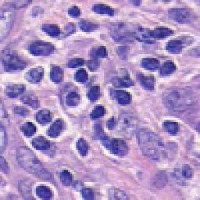

Medical Diagnostics & Research: Researchers and healthcare providers can use LDANN-BASIC to assist in the identification of lymphocyte classes, helping to diagnose diseases like leukemia or lymphoma more efficiently and enhancing our understanding of the immune system.

Pharmaceutical Development & Drug Testing: The model can be employed in pharmaceutical labs to study the effects of new drugs on lymphocyte populations, contributing to the development of more effective medications or therapies targeting specific immune conditions.

Automated Clinical Laboratory Systems: LDANN-BASIC can be integrated into automated image analysis workflows within clinical laboratories, streamlining the process of analyzing patient samples and reducing the risk of human error in lymphocyte classification.

Educational Purposes: The model can serve as a teaching tool for medical students, clinical laboratory scientists, and immunology researchers to learn and visually understand different types of lymphocytes, thereby improving their skills and knowledge in the field of histology and pathology.

Remote and Telemedicine Diagnostics: LDANN-BASIC can be used in remote healthcare settings or telemedical diagnostic systems, enabling healthcare professionals to analyze blood samples from patients even if they are located in rural or remote areas with limited access to specialized labs.